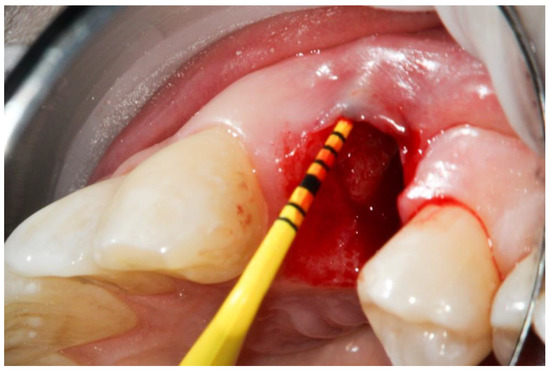

2. Materials and Methods

Histological Analysis